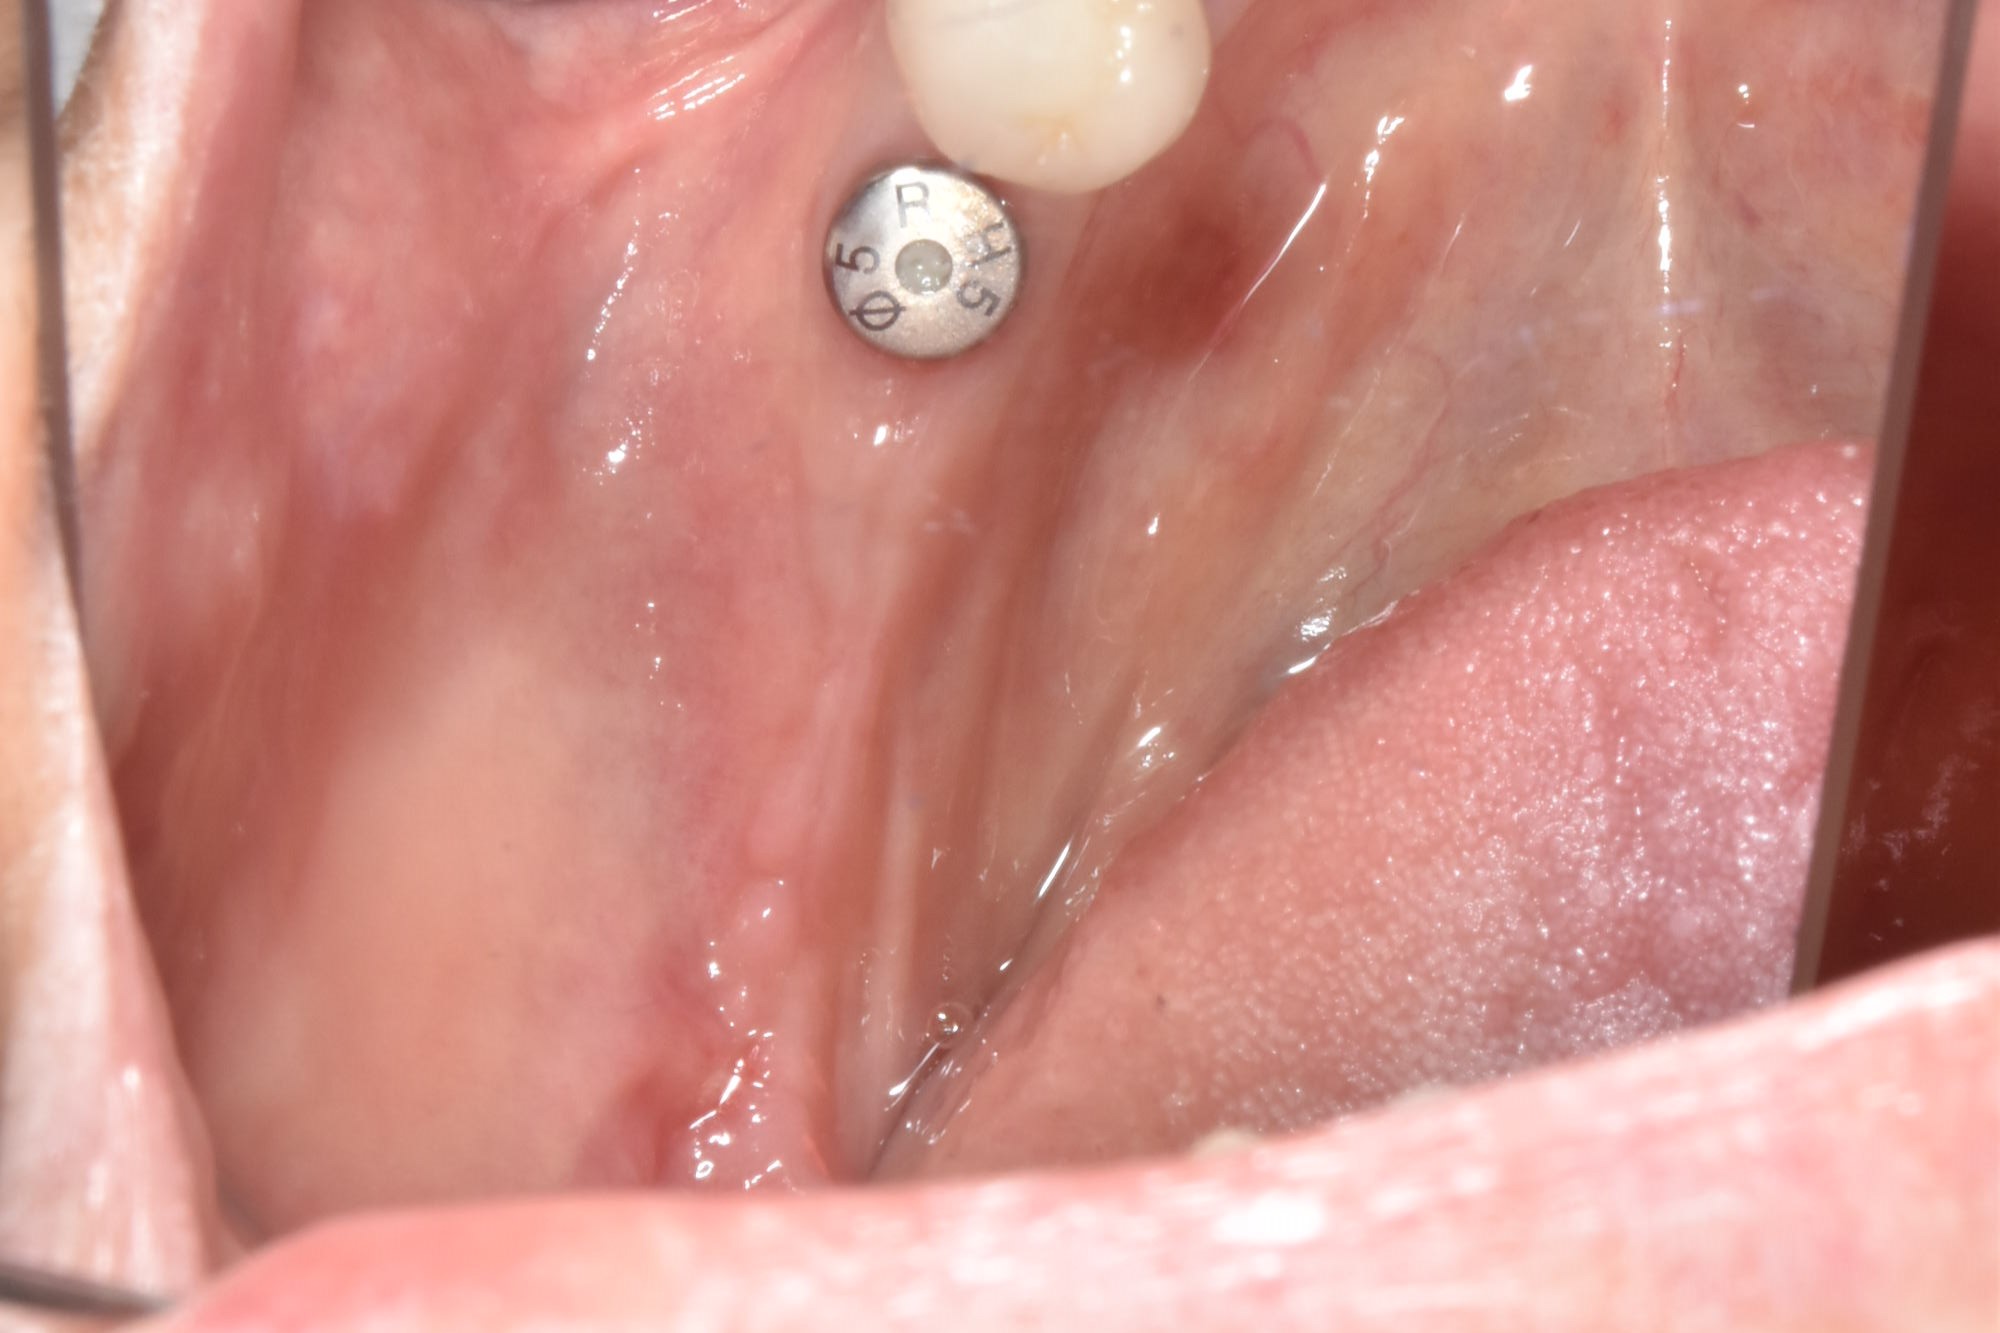

牙齦移植術(補肉)

手術案例

術前加術後案例

案例三